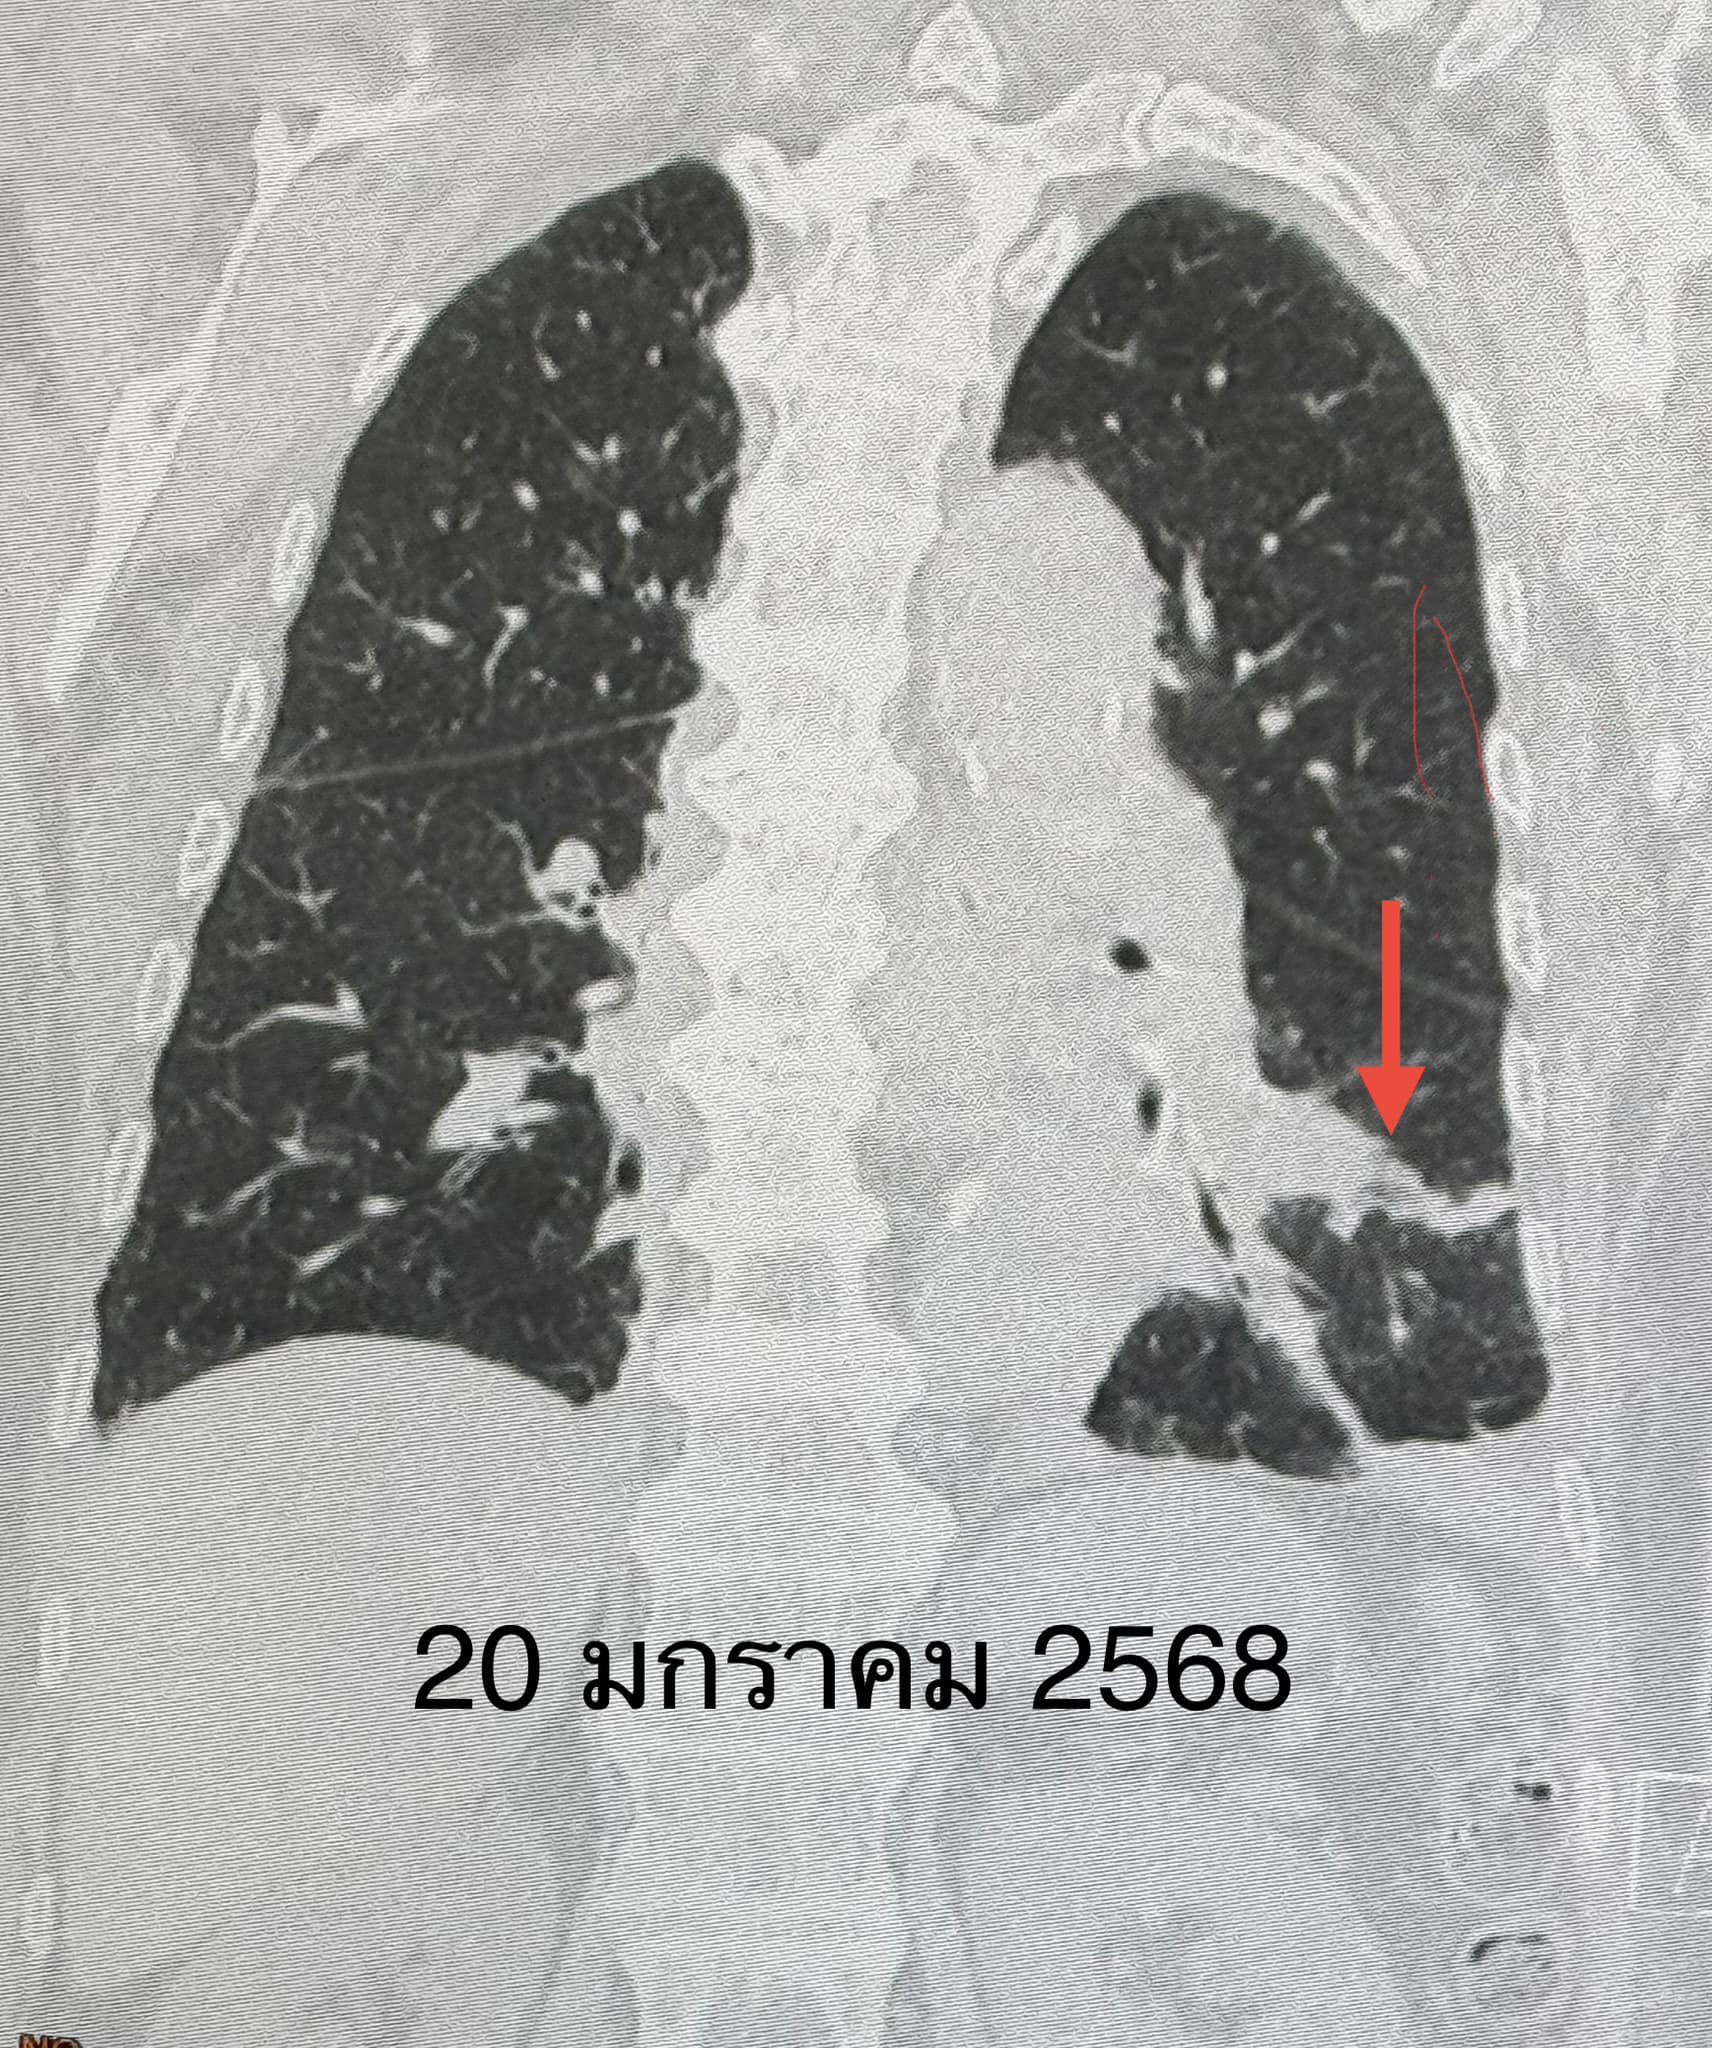

“ตรวจร่างกาย ระดับออกซิเจนที่ปลายนิ้วต่ำ 87% ต้องให้ออกซิเจน 2 ลิตร/นาที ไม่มีไข้ ฟังปอดมีเสียงผิดปกติเล็กน้อยที่ปอดข้างซ้ายด้านล่าง เจาะเลือด เม็ดเลือดขาวในเลือดปกติ เอกซเรย์ปอดมีฝ้าขาวในปอดข้างซ้ายด้านล่าง (ดูรูป) ทำคอมพิวเตอร์ปอดยืนยันว่ามีฝ้าในปอดข้างซ้ายด้านล่าง และมีน้ำในช่องเยื่อหุ้มปอดเล็กน้อย (ดูรูป) ตรวจเลือดเม็ดเลือดขาวปกติ แยงจมูกส่งตรวจรหัสพันธุกรรมเชื้อ 22 สายพันธุ์ไม่พบเชื้อ ส่งเลือดตรวจ Legionella pneumophila Antibody IgM positive 1:200”

“วินิจฉัย: ติดเชื้อแบคทีเรียลีจิโอเนลลา นิวโมฟิลา Legionella pneumophila ทำให้ปอดอักเสบ ให้ยา azithromycin และ levofloxacin คนไข้ดีขึ้น ไม่ไอ ไม่เหนื่อย ระดับออกซิเจนปกติ ไม่ต้องใช้ออกซิเจน วันที่ 26 มกราคมเอกซเรย์ปอดกลับมาเป็นปกติ (ดูรูป)”